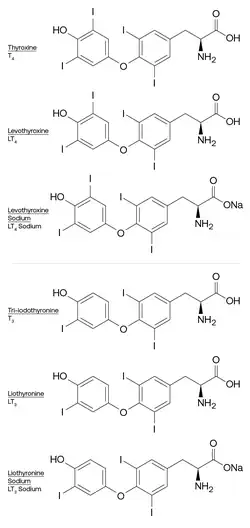

Managing hormone levels

| Endogenous | Synthetic | |

|---|---|---|

| T3 | Tri-iodothyronine | Liothyronine |

| T4 | Thyroxine | Levothyroxine |

Hypothyroidism caused by Hashimoto's thyroiditis is treated with thyroid hormone replacement agents such as levothyroxine (LT4),[20] liothyronine (LT3),[5] or desiccated thyroid extract (T4+T3).[67] In most cases, the treatment needs to be taken for the rest of the person's life.[20]

The standard of care is levothyroxine (LT4) therapy, which is an oral medication identical in molecular structure to endogenous thyroxine (T4).[20] Levothyroxine sodium has a sodium salt added to increase its gastrointestinal absorption.[68] Levothyroxine has the benefits of a long half-life[69] leading to stable thyroid hormone levels,[70] ease of monitoring,[70] excellent safety[70][71] and efficacy record,[65] and usefulness in pregnancy as it can cross the fetal blood-brain barrier.[13]

Levothyroxine dosing to normalise TSH is based on the amount of residual endogenous thyroid function and the patient's weight, particularly lean body mass.[13] The dose can be adjusted based upon each patient, for example, the dose may be lowered for elderly patients or patients with certain cardiac conditions, but is increased in pregnant patients.[10] It is administered on a consistent schedule.[20] Levothyroxine may be dosed daily or weekly, however weekly dosing may be associated with higher TSH levels, elevated thyroid hormone levels, and transient "echocardiographic changes in some patients following 2-4 h of thyroxine intake".[72][73]

Some patients elect combination therapy with both levothyroxine and liothyronine (which is identical in molecular structure to tri-iodothyronine) however studies of combination therapy are limited,[5] and five meta-analyses/reviews "suggested no clear advantage of the combination therapy."[13] However, subgroup analysis found that patients who remain the most symptomatic while taking levothyroxine may benefit from therapy containing liothyronine.[13]